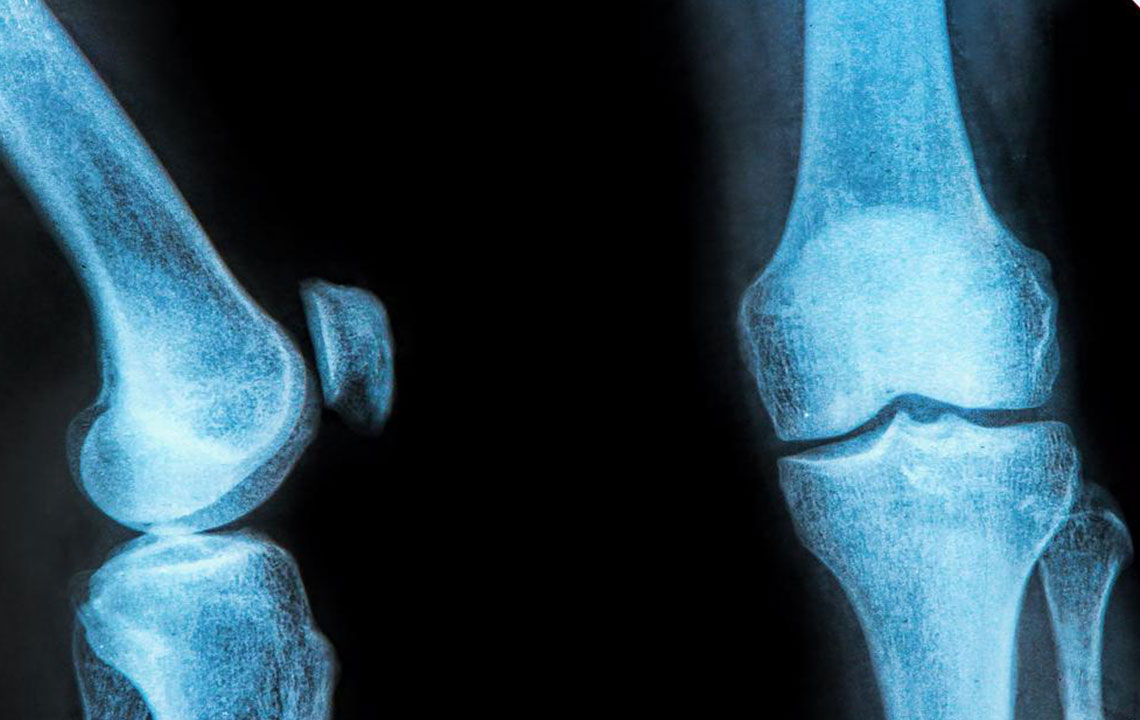

Causes and Prevention of Pain Behind the Knee

The pain at the back of the knee happens due to a lot of reasons. Some of its remedies are pretty common while some need serious medical treatment. The knee bears a lot of impact from the everyday activities. This damage can be avoided by reducing strain on the joint. The treatment of the leg pain behind the knee will vary depending on your condition.